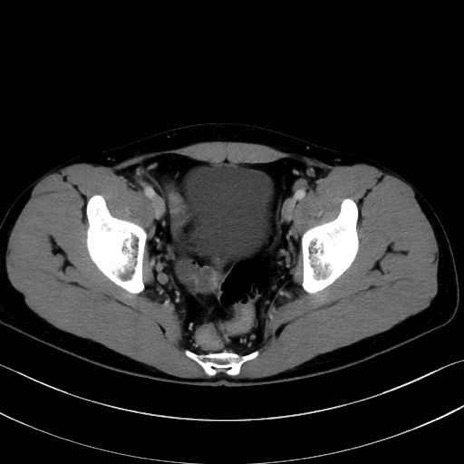

精嚢(seminal vesicle)のCT画像における解剖

症例

【症例】20歳代 男性 スクリーニング